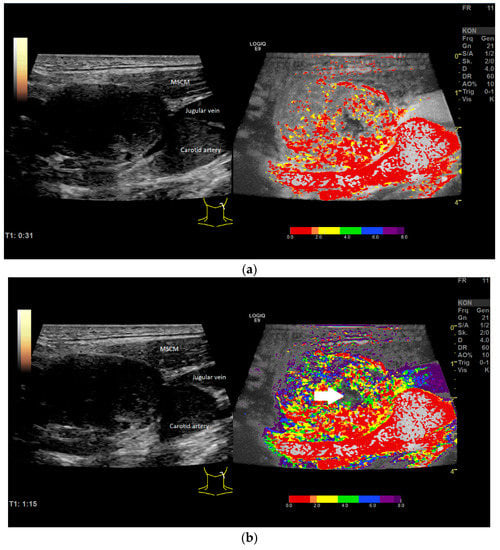

| CEUS | Perfusion and enhancement dynamics (Wash-in/Wash-out) | Time–Intensity Curve analysis with Time-to-Peak and Area-under-the-Curve; two ROI in the center, four at the margin of the LN and two in the surrounding soft tissue (outside of vessels). For the correct placement of ROI, only positive values were accepted (adjustment for artefacts). The diameter of each ROI was 2–3 mm. Additionally parametric evaluation of the perfusion kinetics. |